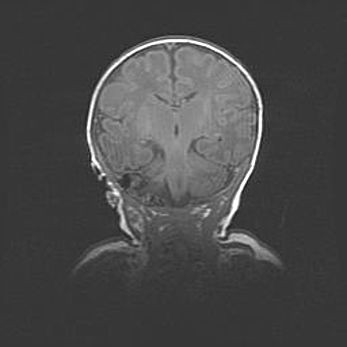

Наружная гидроцефалия с возможной атрофией височных областей.

Возраст: 28 дней

Вес: 3670 г

Пол: мужской

Окружность головы: 38 см

Срок гестации: 40 недель

Гидроцефалия головного мозга у новорожденных – это заболевание, которое характеризуется скоплением избыточного количества спинномозговой жидкости в желудочковой системе головного мозга в результате затруднения её перемещения от места выработки к месту поглощения в кровеносную систему или вследствие нарушения абсорбции. При открытой наружной форме гидроцефалии у новорожденных расширяются и переполняются субарахноидные пространства.

При нормотензивных  формах,  которые,  как  правило,  являются  следствием  перенесенных ишемических  повреждений  паренхимы  мозга,  возможно  сочетание микроцефалии  с нормотензивной гидроцефалией. В основе данных изменений лежит атрофия больших полушарий с преимущественной  локализацией  в  лобно-височных  областях.